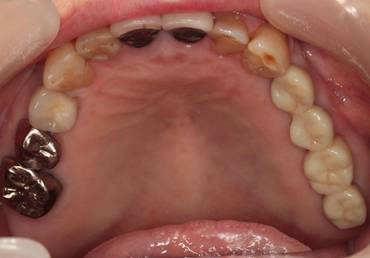

歯周病で抜歯せざるを得ず、インプラントを希望されたケース(使用インプラントはスプライン)

術前。すべての歯が歯周病の末期状態でブリッジ全体がうごいて噛めないとの訴え。右上の犬歯が腫れていました

固定式のブリッジが入っていましたが歯周病で動いています

下顎前歯部には歯石の沈着がみられます